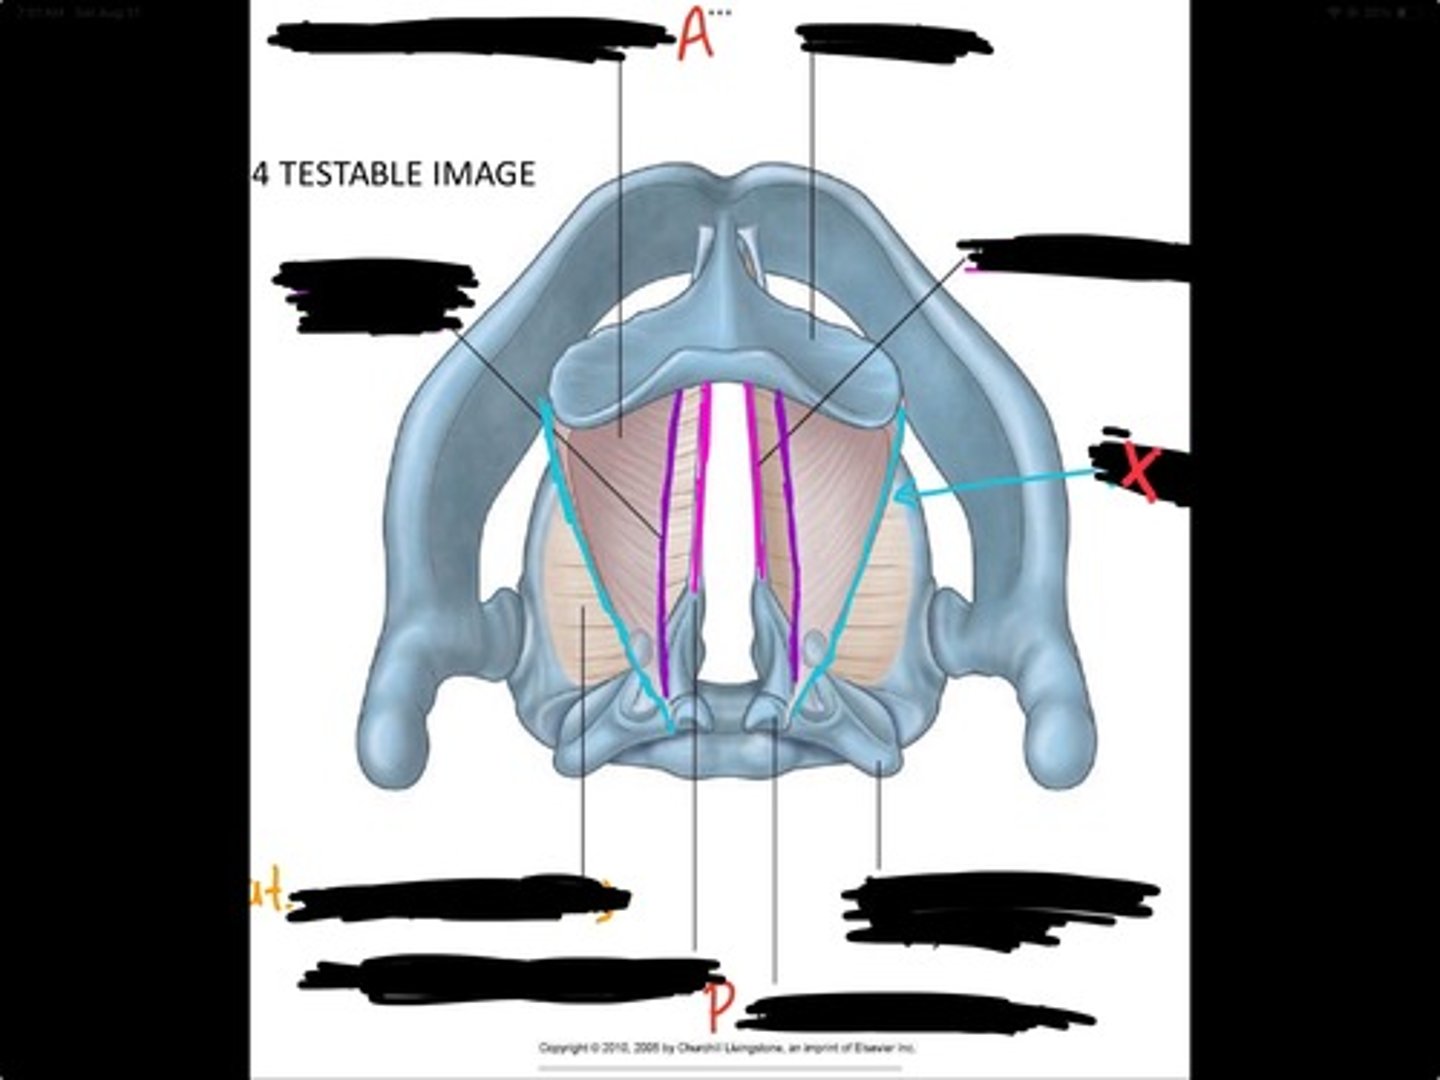

Vocal process of arytenoid

Conus elasticus

Vestibular ligament

Quadrangular membrane

Epiglottis

vocal ligament

Aryepiglottic ligament

Muscular process of arytenoid

Corniculate cartilage

Posterior crico arytenoid

oblique arytenoid

transverse artyenoid

Rima glottidis

Vocal ligament

Vocalis muscle

Lateral cricothyroid ligament

Lateral cricoartenoid